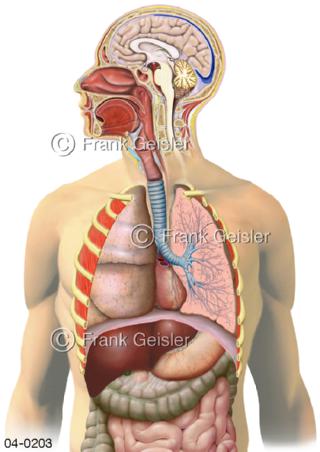

Bildergalerie Topografie Organe

Bilder zur topografischen Anatomie, die Lage der Organe und die Strukturen nach ihren räumlichen Lagebeziehungen zueinander, Übersicht der inneren Organe im Kopf und im Rumpf, Topografie der Organe im Brustraum (Thorax) und im Bauchraum (Abdomen)